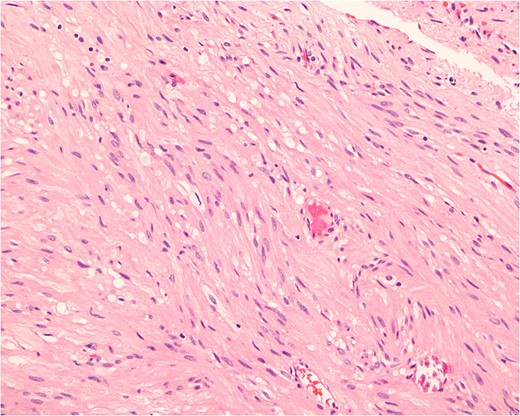

Histopathologically, the tumor consists of cells resembling normal smooth muscle cells. The cells are uniform, elongated and spindle-shaped, and exhibit a cigar-shaped nucleus (hematoxylin & eosin stain, magnification ×200).